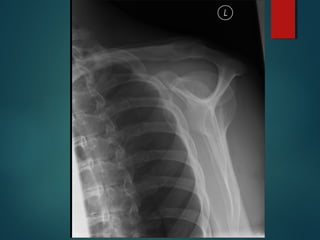

A routine AP shoulder radiograph shows overlap of the

anterior and the posterior glenoid rims. A true AP

radiograph demonstrates superimposition of the anterior

and the posterior glenoid rims, producing an excellent

view of the glenohumeral joint.

Normal Shoulder AP view